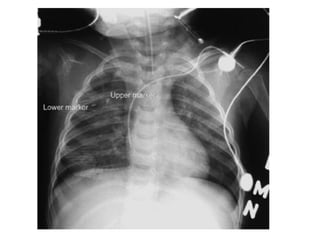

Hemothorax

Chest x ray